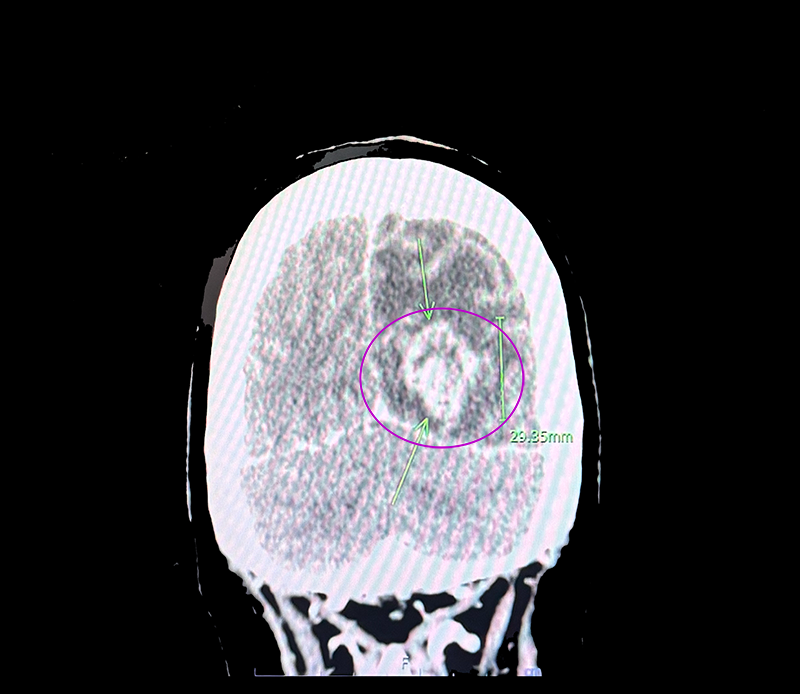

เราก็ได้แต่หันไปทำหน้างง ๆ ใส่แล้วเดินกลับเตียงไป ไม่เข้าใจว่าเขาหมายถึงอะไรกัน จนกระทั่งเมื่อมาเห็นไฟล์ภาพ CT Scan นั่นแหละถึงรู้ว่าเนื้องอกขนาดประมาณ 3×3 เซนติเมตรอยู่ในหัวด้านหลัง เหนือท้ายทอยเล็กน้อย มันเบียดแน่นไปหมด ดูพร้อมจะระเบิดได้ทุกเมื่อเขียวละ

อะ ๆ แอบเอารูปให้ดูนิดหนึ่ง เห็นก้อน ๆ ตรงนั้นมั้ย ที่วงสีแดง ๆ ไว้นั่นแหละ ภาพมันจะกลับด้านซ้ายขวา (Mirror) ก้อนเนื้ออยู่ด้านซ้าย อันนี้น่าจะเป็นมุมมองจากด้านหลัง เอ๊ะ…จะว่าไป ภาพนี้พิสูจน์แล้วนะคะว่าดิฉันมีสมองค่ะ ฮา ๆ

เอาละ กลับมาที่เรื่องของเราดีกว่า สรุปแล้วเรามีเนื้องอกในสมอง อยู่ใกล้ประสาทตาด้านซ้าย เบียดตาซ้ายจนเข และคงเบียดระบบประสาทการเคลื่อนไหวในช่วยสามเดือนก่อนด้วย ต้องได้รับการผ่าตัดเอาออกค่ะ